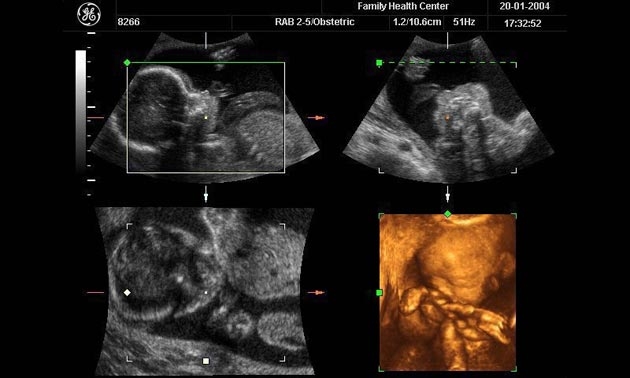

ใช้มือถือถ่ายครรภ์ อาจทำให้การตรวจอัลตราซาวนด์สับสน

สมาคมและวิทยาลัยการถ่ายภาพด้วยรังสี ได้ออกคำเตือนว่า แพทย์ไม่ควรจะยอมให้มีการถ่ายภาพด้วยโทรศัพท์มือถือหรือกล้องวีดิโอ การตรวจครรภ์ด้วยวิธีคลื่นเสียงความถี่สูง

สมาคมกล่าวว่า ได้รับรายงานว่า มีผู้มีครรภ์ ต้องการอยากจะบันทึกการตรวจท้องของตนมากขึ้น การกระทำดังกล่าวอาจทำให้เจ้าหน้าที่ผู้ตรวจเกิดความไขว้เขว และอาจมองข้ามอาการอันจำเป“นต่อชีวิตของทารกในครรภ์ที่กำลังเติบโตไป

โฆษกของสมาคมแสดงความเห็นว่า เพราะความก้าวหน้าของเทคโนโลยี ทำให้มีความ ต้องการที่จะบันทึกเรื่องนี้ นับวันจะเพิ่มมากขึ้น จึงได้ออกคำแนะนำไปยังผู้ที่มีหน้าที่เกี่ยวข้องว่า ควรจะปฏิบัติอย่างไร หากถูกคนไข้ขอร้อง จะขอถ่ายภาพเอาไว้

การทำเช่นนั้น นอกจากจะทำให้เจ้าหน้าที่ขาดสมาธิในยามที่ต้องใช้สมาธิมากที่สุดแล้ว ยังอาจจะทำให้ เกิดคดีความขึ้นได้ หากปรากฏว่ามีการตรวจพบอาการผิดปกติขึ้น แต่ไม่ได้มีการดำเนินการใดๆ.